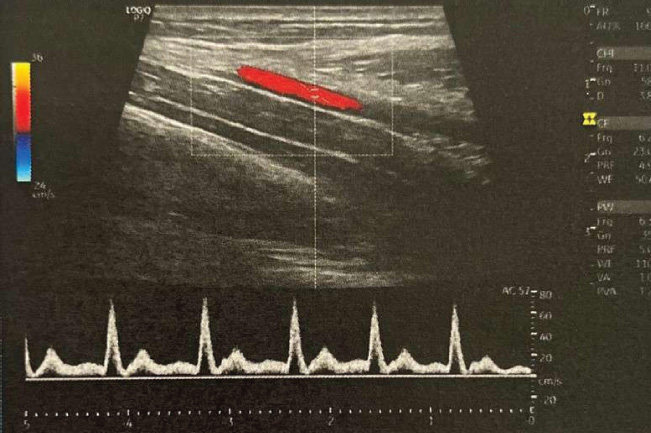

Fig. 6. Image of the abdominal aorta of a cat, showing the sample volume, ultrasound beam, and main flow vector, with the latter overlaid and parallel to the vessel being evaluated with spectral Doppler. Source: Personal archive, 2025.

Pulsed spectral Doppler signals

This technique measures flow velocity using piezoelectric crystals that emit ultrasound sound pulses and analyze the reflected signal. The sample volume (or “gate”) was adjusted in B mode to locate the area of interest (Szatmári, et al., 2001; Carvalho et al., 2008a). The accuracy of the Doppler decreases with angles close to 90°, and the data are processed via Fourier transform to generate graphs with Fd on the vertical axis and time on the horizontal (Carvalho et al., 2008b), as illustrated in Figure 6. The duplex image combines Doppler and B-mode images in real time, facilitating interpretation (Carvalho et al., 2008a).